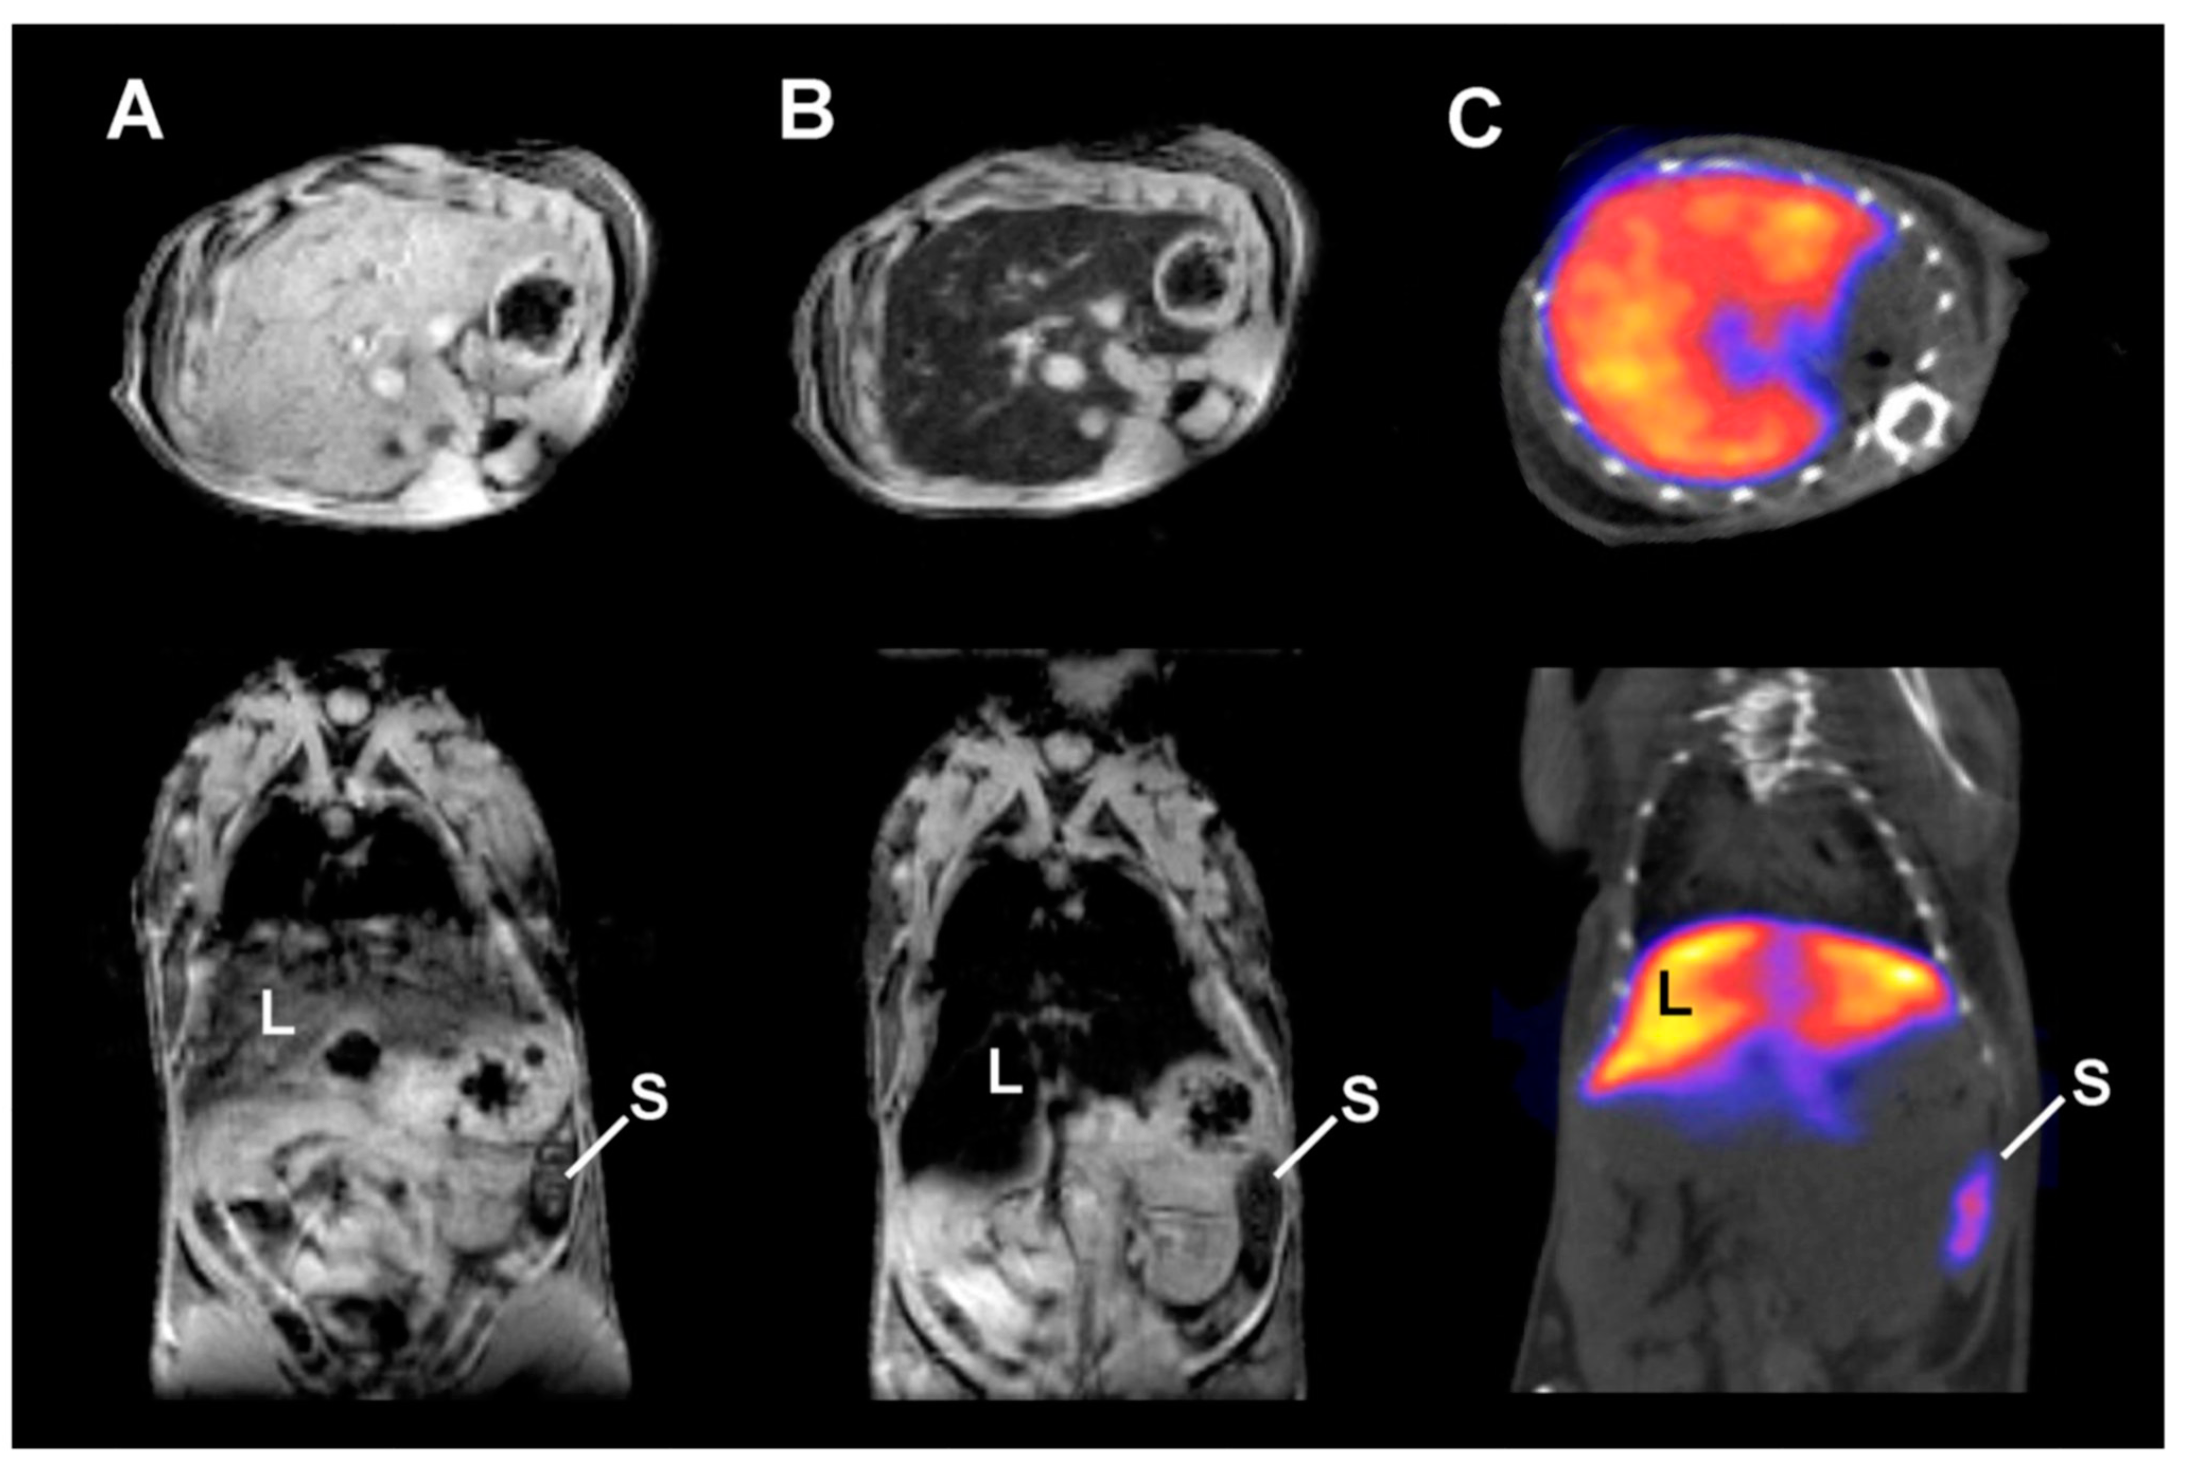

Figure 2.

Representative (A,B) T2*-weighted axial (top) and coronal (bottom) MRI data of 99mTc-DPA-ale-Endorem: (A) before injection; (B) 15 min post-injection (p.i.); (C) Representative SPECT-CT image of the same mice 45 min p.i. (L: liver, S: spleen). (Reprinted with permission from [34]. Copyright 2011 American Chemical Society).